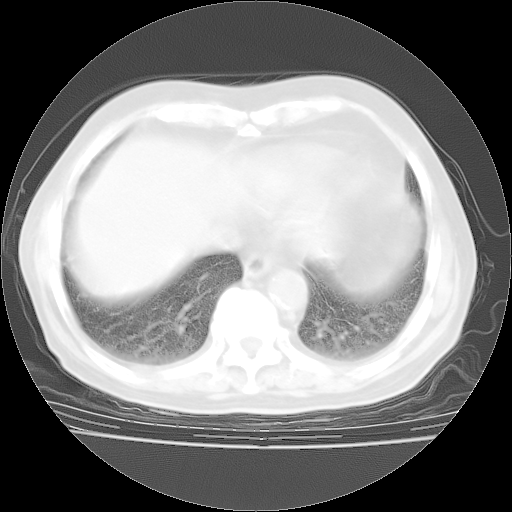

4月28日肺部CT——再次出现类似去年5月9日——透光度降低,“间质性”改变。

4月28日肺部CT——再次出现类似去年5月9日——磨玻璃样、间有“粟粒样”改变。

4月28日肺部CT